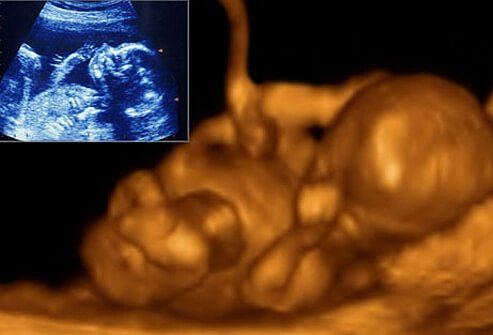

• Second Month

Second Month

The zygote is about 1/4 inch long and has distinct, slightly webbed fingers. Face, eyes ears and limbs have developed. Veins are clearly visible. The heart has divided into right and left chambers. Zygote changes into an embryo at the end of eight weeks.